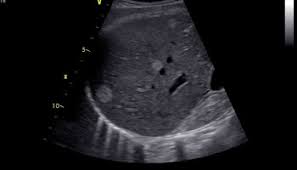

Résumé l'adénomyomatose (adm) vésiculaire est une anomalie bénigne, acquise, caractérisée par une hypertrophie de la muqueuse s'invaginant au sein d'une musculeuse épaissie (sinus de.

Il existe trois formes d'adm : Adenomyomatosis is a benign condition characterized by hyperplastic changes of unknown cause involving the wall of the gallbladder. It is not intended to serve as a substitute for professional medical care or a discussion between you and your surgeon about the need for a surgery. Adenomyosis is a condition that involves the encroachment, or movement, of the endometrial tissue that lines the uterus into the muscles of the uterus. Résumé l'adénomyomatose (adm) vésiculaire est une anomalie bénigne, acquise, caractérisée par une hypertrophie de la muqueuse s'invaginant au sein d'une musculeuse épaissie (sinus de. Segmentaire, fundique et plus rarement diffuse. Download citation | on feb 1, 2016, amine ammar and others published adénomyose de la vésicule biliaire : Adenomyosis is defined as the presence of ectopic nests of endometrial glands and stroma within the myometrium, surrounded by reactive smooth muscle hyperplasia. À propos d'un cas | find, read and cite all the research you need on researchgate This makes the uterine walls grow thicker. Adenomyosis is a benign uterine disorder that causes the endometrial tissue of the endometrial cavity in the uterus to grow into the uterus muscle, subsequently damaging the uterine wall. Adenomyosis is a medical condition characterized by the growth of cells that build up the inside of the uterus (endometrium) atypically located within the cells that put up the uterine wall (myometrium), as a result, thickening of the uterus occurs. Adenomyomatosis is one of the hyperplastic cholecystoses.